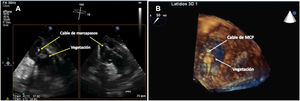

Infección sistémicaSe asocia a semiología clínica de infección como fiebre, escalofríos, malestar general o incluso signos de sepsis (taquicardia, hipotensión, shock...) y/o hemocultivos repetidamente positivos. En el 70-80% de los casos los pacientes tienen concomitantemente signos de infección localizada. Dentro de las infecciones sistémicas cabe destacar si afectan al cable en su porción endovascular y/o intracardiaca (fig. 2), o incluso a las válvulas cardíacas, lo que ocurre aproximadamente en un 10-25% de los casos.

Los pacientes con endocarditis asociada a DEC se diagnostican mediante la aplicación de los criterios de Duke modificados1–4. La presencia de vegetaciones en los cables o en las válvulas evidenciables en el estudio ecocardiográfico es más frecuente en la válvula tricúspide, reportándose hasta en un 10-25% del total de las endocarditis sobre DEC.

Ecocardiografía transtorácica y ecocardiografía transesofágicaLa ecocardiografía es la piedra angular del proceso diagnóstico de la afectación intracardiaca de DEC al poner en evidencia las vegetaciones en los electrodos (fig. 3) o en las válvulas cardiacas1–4. La ecografía transtorácica (ETT) puede identificar bien las vegetaciones sobre la válvula tricuspídea por la accesibilidad de las estructuras de corazón derecho y proporciona información útil sobre la existencia de derrame pericárdico, la disfunción ventricular y las valoraciones de la presión vascular pulmonar12,14. Sin embargo, su sensibilidad para detectar vegetaciones sobre los cables no va más allá de un 20-30%, por lo que el diagnóstico de las vegetaciones en los cables de los DEC debe realizarse mediante un ecocardiograma transesofágico (ETE) que tiene una sensibilidad del 60-90%, siendo por tanto una prueba obligada para discernir entre una infección puramente local y una complicada o sistémica1,5. La realización del ETE permite además la cuantificación del defecto valvular, si está presente, medir el tamaño de las vegetaciones y el seguimiento tras la extracción del electrodo14–15. De todas formas, la sensibilidad nunca es del 100% y, en ocasiones, bien por el estado clínico del paciente, las limitaciones anatómicas o la patología asociada (varices en el paciente cirrótico, estenosis esofágica, enfermedad del cavum...) no va a ser posible realizarla, por lo que en algunas circunstancias solo dispondremos de un ETT, y son precisas otras técnicas diagnósticas asociadas para establecer el diagnóstico definitivo. Por otro lado, en determinadas circunstancias resulta imposible diferenciar entre un trombo, una masa de fibrina o una vegetación séptica sin el contexto clínico adecuado, con una cifra no desdeñable de falsos positivos, en torno al 10-15%7,13–17.